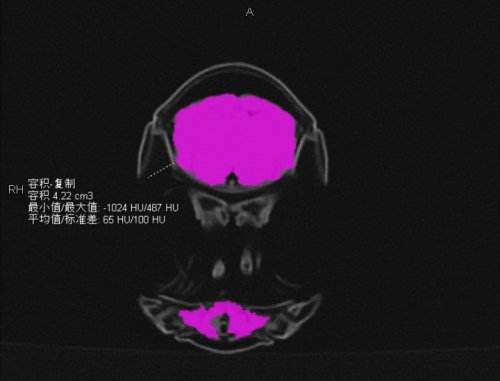

可食用部分:虾肉体积为 4.22ml,平均密度为 65HU,占全虾体积比 11.42%。

虾肉体积为 4.22 ml,平均密度为 65HU(作者供图)